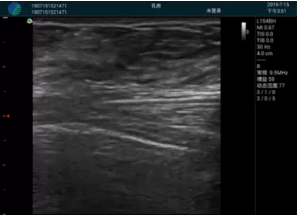

M20實(shí)時(shí)引導(dǎo):向包塊后方間隙注射利多卡因

確定進(jìn)針路徑并實(shí)時(shí)監(jiān)測(cè)抽吸針與腫塊位置關(guān)系

抽吸針進(jìn)入腫塊內(nèi)部進(jìn)行旋切

抽吸過(guò)程中可見(jiàn)腫塊明顯縮小,并根據(jù)腫塊位置改變針道位置

抽吸旋切后再進(jìn)行超聲復(fù)查,原腫塊區(qū)域未見(jiàn)殘留組織及出血